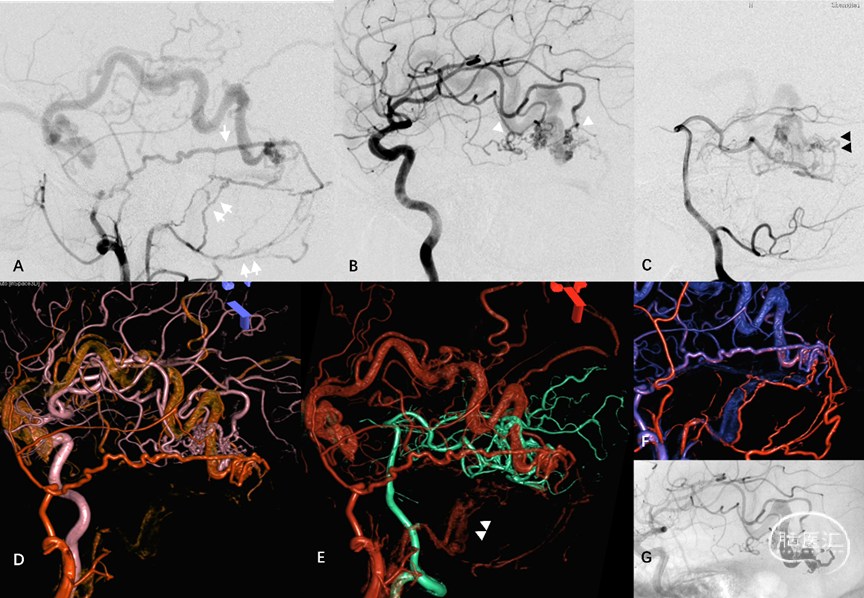

图16. 侧窦区桥静脉型DAVF典型血管构筑。MMA(白箭)、脑膜后动脉(双白箭)、大脑中动脉硬膜支(白箭头)及大脑后动脉硬膜支(黑双箭头)向Labbe桥静脉硬膜内段汇集(A-C)。MMA与颈内动脉(ICA),MMA与椎动脉,MMA与咽升动脉分别行双容积融合成像(D-F)。经动脉栓塞后Onyx胶在桥静脉及软膜静脉起始部的铸型(G)

图 17. 天幕缘组DAVF典型血管构筑。A-D:ECA发出的供血分支向天幕缘桥静脉(星号)汇集,经扩张的桥外侧静脉向对侧同名静脉引流。颌内动脉超选择造影(B)显示翼管动脉管径增粗,移行为硬膜静脉结构(双白箭)再汇入共同静脉端。F-G:TOF及增强磁共振、DAVF与颅骨的双容积融合成像显示桥静脉起始部(星号)位于岩尖的天幕游离缘。G:TAE后Onyx胶在桥静脉起始部的铸型

图 18. 上矢状窦区桥静脉型DAVF典型血管构筑。A-B:双侧MMA(单、双箭)向大脑上静脉桥静脉汇集。C:TAE后Onyx胶在硬膜动脉网(单、双箭)及桥静脉(双白箭头)的铸型。D:患者合并SSS中部血栓

图19. 髁前区DAVF典型血管构筑。A-C:枕动脉、咽升动脉供血分支向颈静脉结节静脉丛(JTVC)(白箭)汇集,经岩下窦向海绵窦、侧裂浅静脉逆流。D:ECA主干与咽升动脉双容积融合成像。E:位于骨内的JTVC(白箭)是髁前区板障-导静脉型DAVF的初级静脉结构。F:术中利用微导丝与静脉双容积融合成像定位。G-H:TVE闭塞JTVC及髁前静脉,治愈性栓塞DAVF同时保护岩下窦